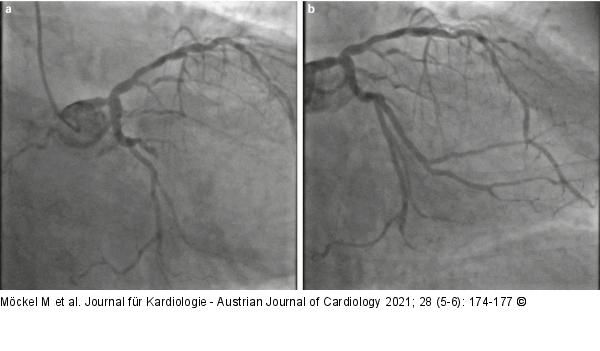

Abbildung 3: Koronarangiographie Koronarangiographie der linken Kranzarterie mit (a) Diagnostik des Verschlusses eines großen Marginalastes der LCX, (b) nach erfolgreicher Rekanalisation und Stentimplantation. |

Koronarangiographie der linken Kranzarterie mit (a) Diagnostik des Verschlusses eines großen Marginalastes der LCX, (b) nach erfolgreicher Rekanalisation und Stentimplantation. |